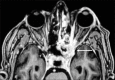

Methods: We conducted a retrospective, interventional study on six consecutive patients with COVID-19 who developed rhino-orbital mucormycosis and were managed at two tertiary ophthalmic referral centers in India between August 1 and December 15, 2020. Diagnosis of mucormycosis was based on clinical features, culture, and histopathology from sinus biopsy. Patients were treated with intravenous liposomal amphotericin B with addition of posaconazole and surgical debridement of necrotic tissue.

Results: All patients were male, mean age 60.5 ± 12 (46.2-73.9) years, type 2 diabetics with mean blood glucose level of 222.5 ± 144.4 (86-404) mg/dL. Except for one patient who was diagnosed with mucormycosis concurrently with COVID-19, all patients received systemic corticosteroids for the treatment of COVID-19. The mean duration between diagnosis of COVID-19 and development of symptoms of mucor was 15.6 ± 9.6 (3-42) days. All patients underwent endoscopic sinus debridement, whereas two patients required orbital exenteration. At the last follow-up, all six patients were alive, on antifungal therapy.